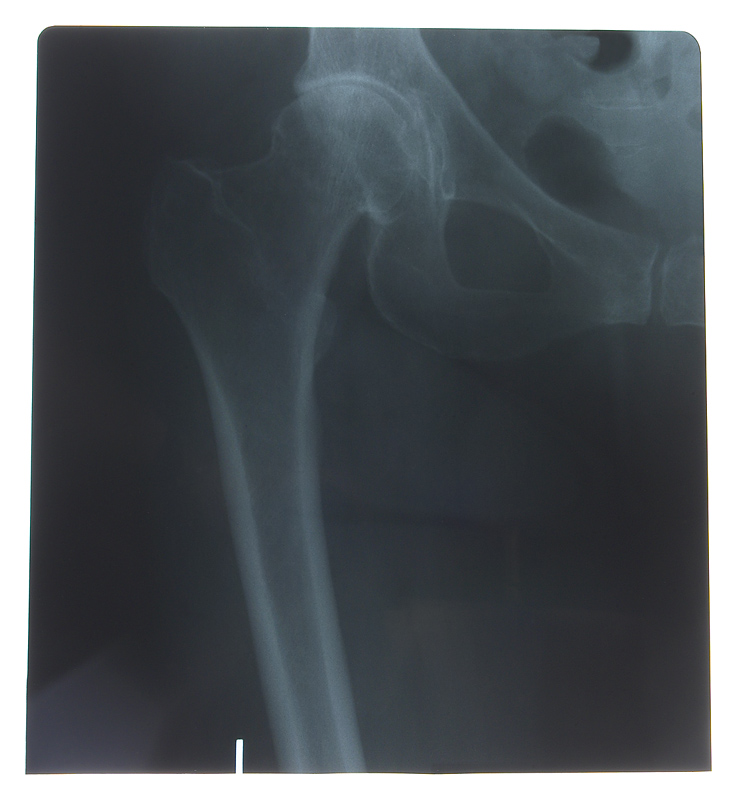

Los huesos que se fracturan más frecuentemente cuando hay osteoporosis son:

· La cadera